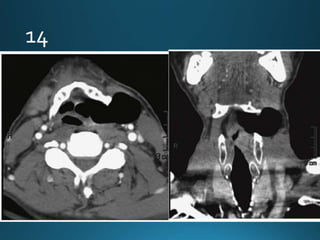

11.

External auditory canal atresia (EACA) is characterised by complete or incomplete

bony atresia of the external auditory canal (EAC)

Findings in the middle ear are variable and the inner ear and inner auditory canal are

typically normal

number of syndromes are associated with external auditory canal atresia 2.These

include:

• Crouzon syndrome

• Treacher Collins syndrome

• Goldenhar syndrome

• Pierre Robin syndrome

External auditory canalatresia (EACA) is characterised by complete or incomplete bony atresia of the external auditory canal (EAC) Findings in the middle ear are variable and the inner ear and inner auditory canal are typically normal number of syndromes are associated with external auditory canal atresia 2.These include: • Crouzon syndrome • Treacher Collins syndrome • Goldenhar syndrome • Pierre Robin syndrome